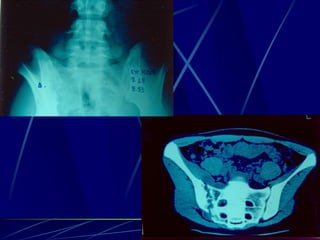

Echinococcus